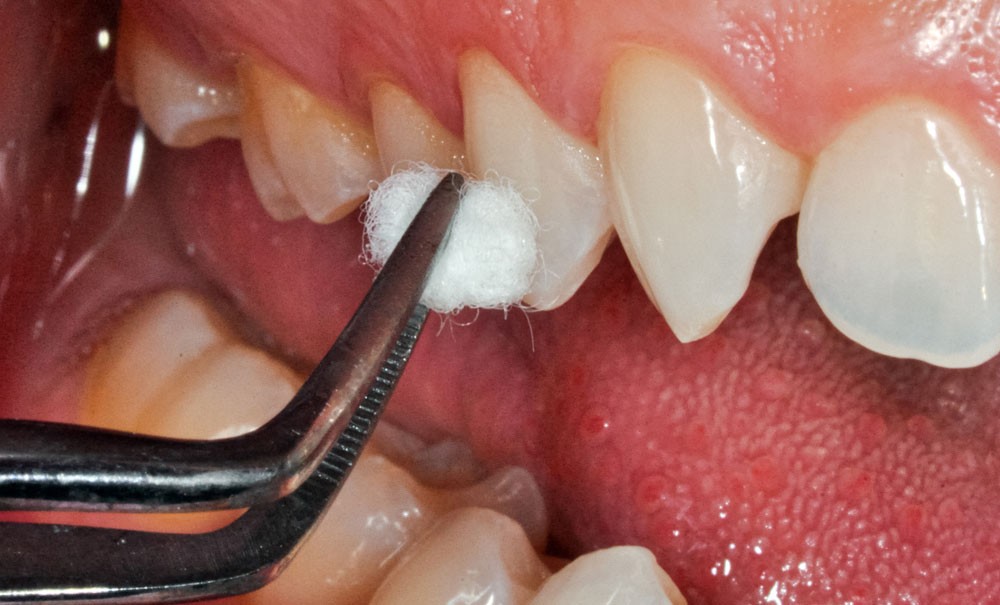

La prise en charge des urgences fait partie intégrante de l’exer­cice courant des chirurgiens-­dentistes. Ses objectifs prin­cipaux sont le soulagement de la douleur et la préservation de toute perte de chance pour un patient qui vient le plus souvent bouleverser l’organisation d’une journée de soins bien planifiée. Dans un temps de prise en charge forcément très limité, il est capital, avant toute action, de poser le bon diagnostic. Il ne s’impose pas toujours de manière évidente et repose sur une bonne analyse des signes cliniques, radiologiques, confrontée aux données de l’anamnèse. Parmi les urgences incontournables qui poussent le patient à consulter, les douleurs pulpaires demandent une prise de décision concernant la préservation de la vitalité de la dent basée sur l’évaluation de la réversibilité de la pulpite. Les auteurs de l’étude clinique rapportée nous rappellent que le test au froid est le plus communément employé pour le diagnostic de la pulpite et pour l’identification de la dent symptomatique. L’absence de la réplication de sensibilités exacerbées au moment de ce test peut poser des difficultés de prise en charge et conduire le chirurgien-dentiste qui doute à différer un acte de soulagement pulpaire (pulpotomie en attente de pulpectomie complète, Ndlr) au risque de donner lieu à des complications encore plus importantes pour le patient.

Les auteurs suggèrent que la prise d’antalgiques préalable à la consultation serait susceptible d’influencer négativement la réponse aux tests de sensibilité et de fausser le diagnostic du praticien. Ils indiquent que plus de 80 % des patients consultant pour des douleurs pulpaires modérées à sévères ont pris des antalgiques et que 65 % de ces cas se déclarent avoir été soulagés par ces médicaments. Considérant leur hypothèse, ils ont mené une étude clinique contrôlée randomisée afin d’évaluer l’effet des deux antalgiques les plus…